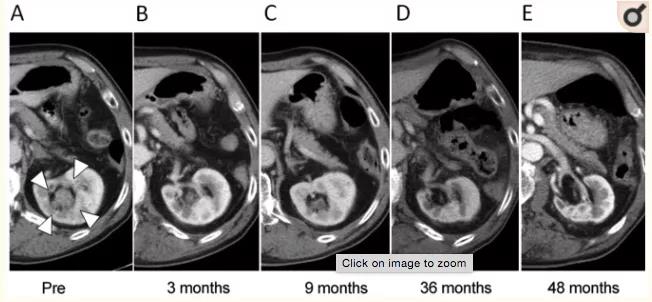

△一名患者质子束治疗之前和之后的CT图像, 在左肾盂(A)中检测到肿瘤,但逐渐缩小(B),在PBT治疗后9个月未检测到肿瘤(C)。(D)大剂量照射的左肾内侧部分缩小,(E)48个月时明显萎缩。尽管观察到受照射肾脏的萎缩性变化,但该名患者左肾的部分肾功能得以保留。